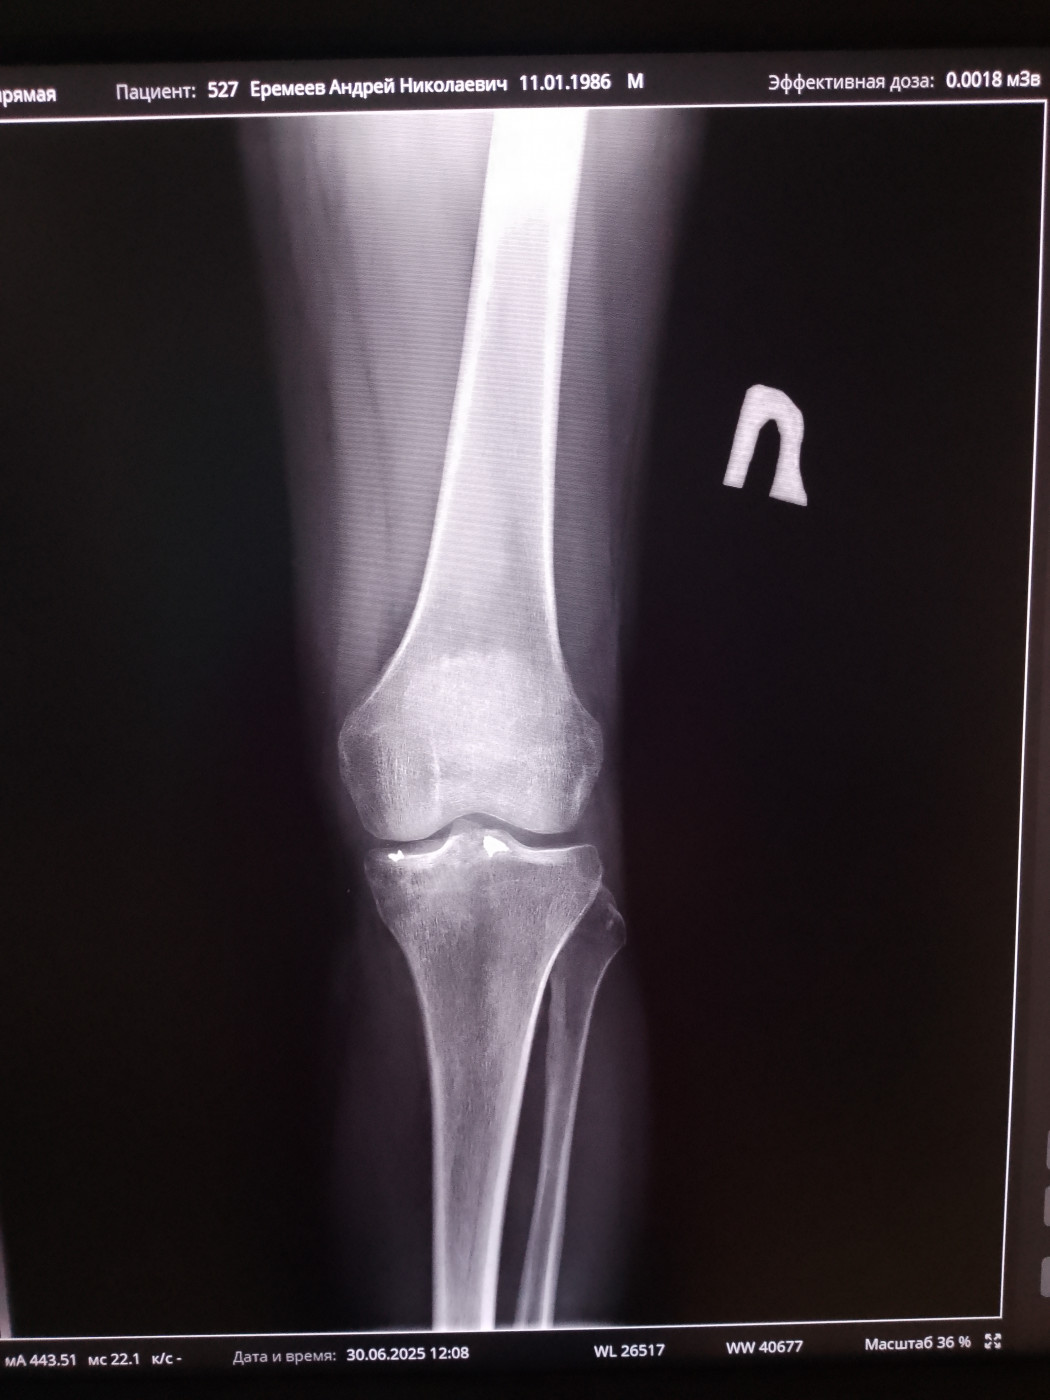

Могут ли комисовать из армии с осколками в коленном суставе